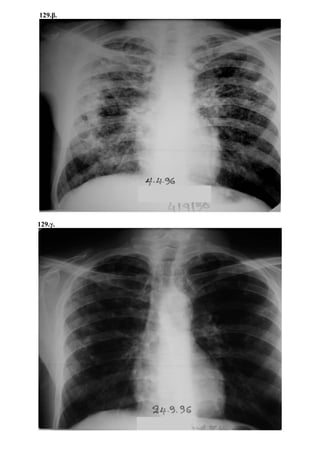

Περίπτωση 21η:

Α/Α Φ Η ΤΡΟΠΟΣ ΔΙΑΓΝΩΣΗΣ ΑΚΤΙΝΟΓΡΑΦΙΑ ΑΝΤΙΦΥΜΑΤΙΚΗ ΑΓΩΓΗ ΔΘ ΕΚΒΑΣΗ

21 Θ 7

ΠΕΛ ΤΕ ΝΣ

+

+ ++ +++

R

ΙΝΗ

Μ

Z S Νοσ.

Σπ.12

ΙΑ

Ιν.Στ. Υπ.Βλ ΕΠ Θ.

21.α.

21.β.

6/9/1996